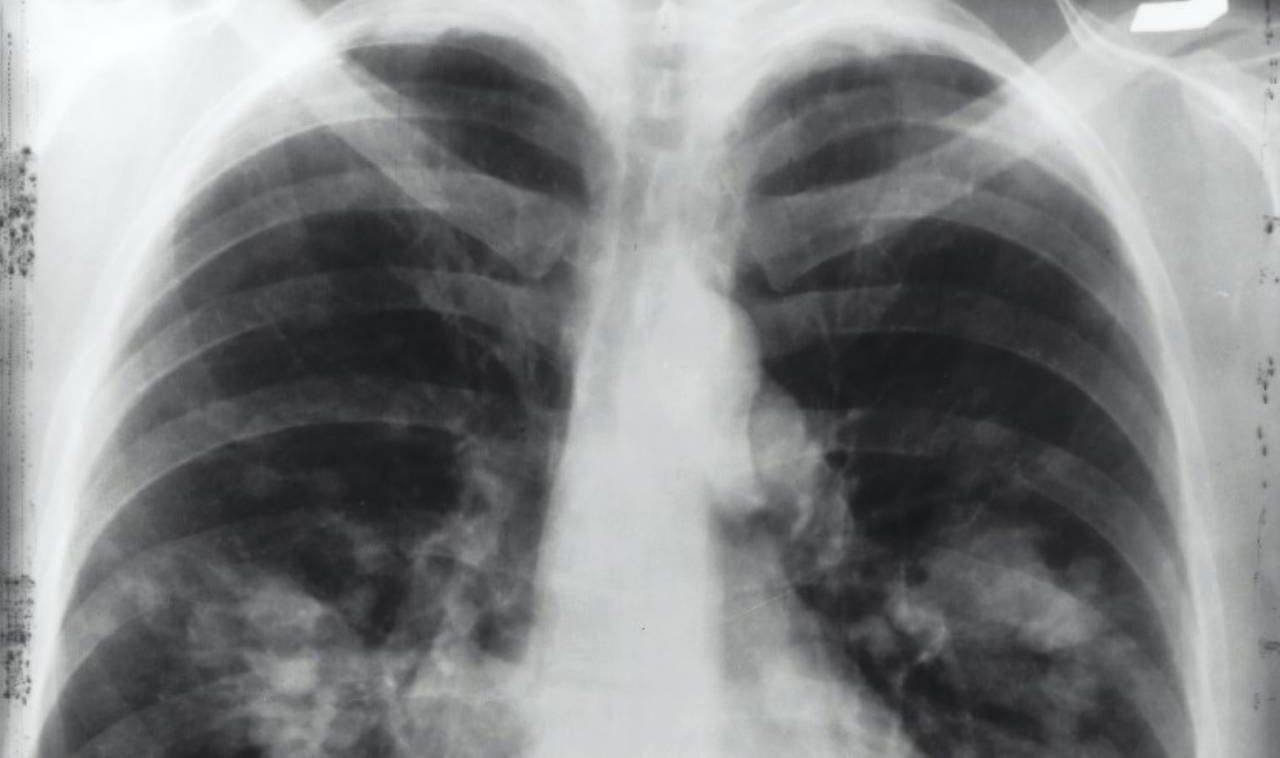

GÖRÜNTÜLEME

Göğüs röntgeni veya bilgisayarlı tomografi (BT) taraması. Astıma eşlik eden yapısal sorunlar veya enfeksiyonlar varsa ortaya çıkmasını sağlıyor.